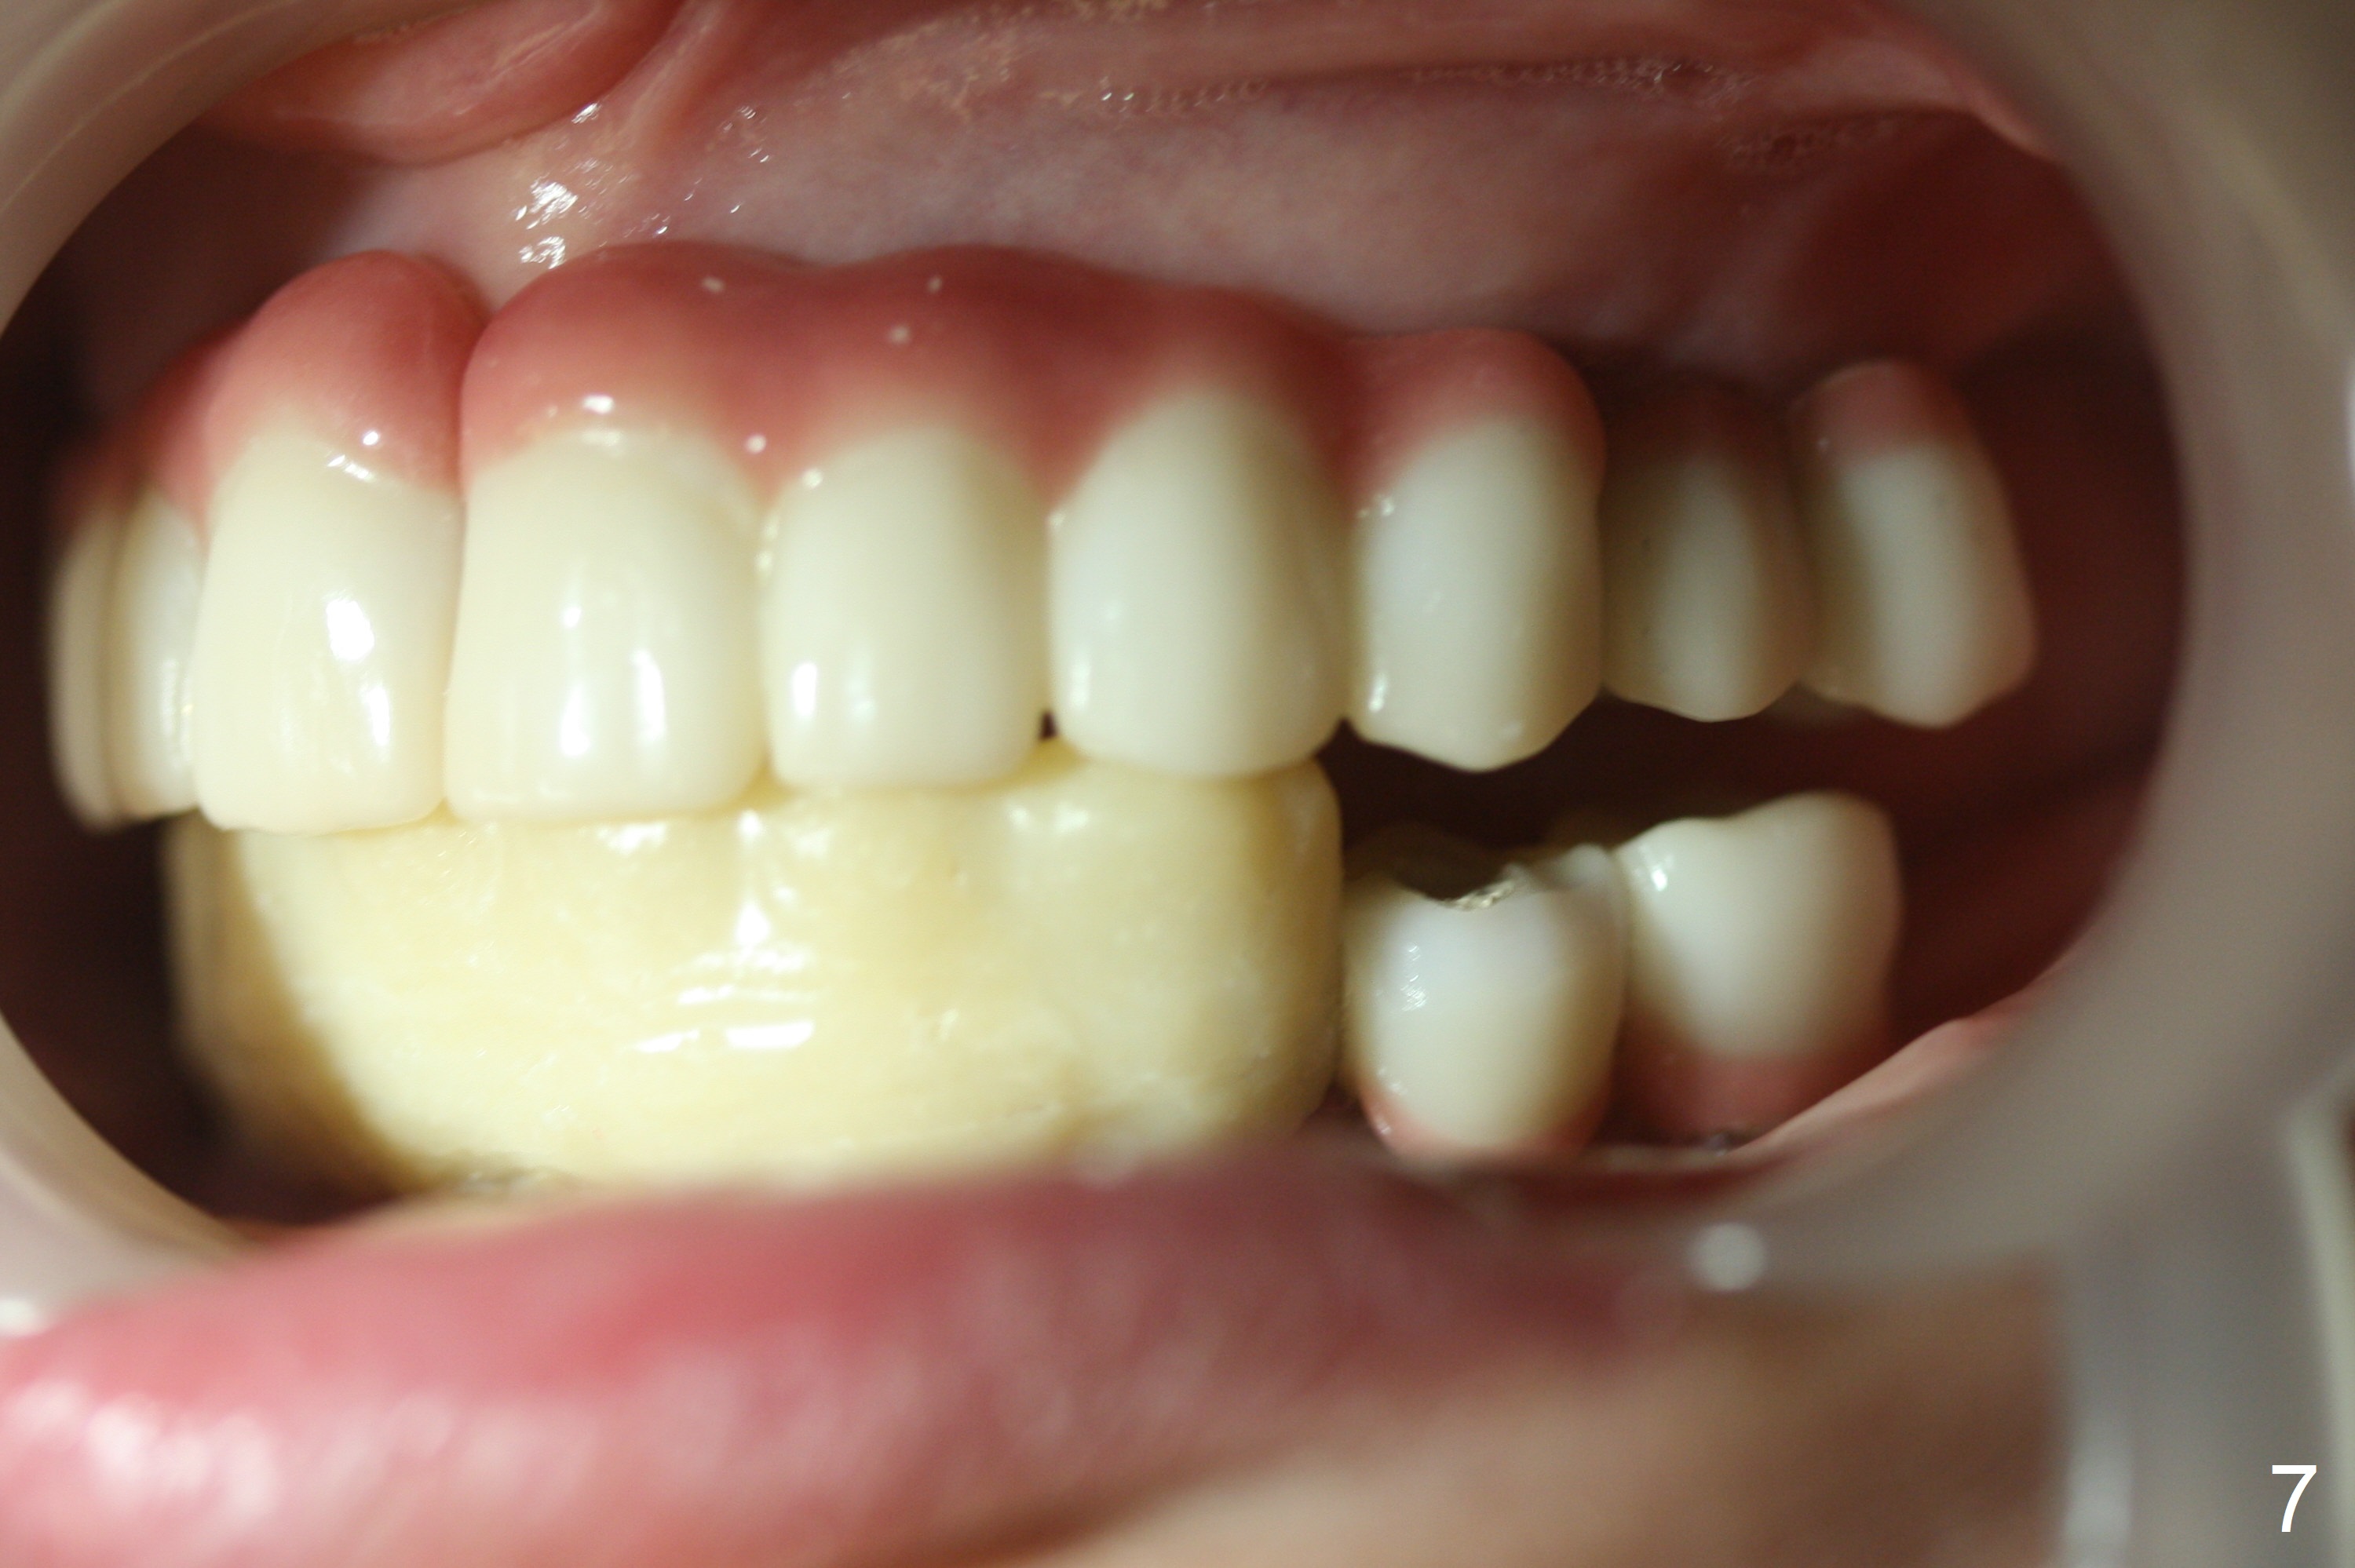

A 56-year-old woman with atrophic jaws requests redoing lower implant restoration (in function 1 year) for cosmetic reason and placing an implant at #19 (because she could not masticate on the left). Note the discrepancy between CR and CO (Fig.1,2). There is gingival hypertrophy at #31 (Fig.3), while the anterior restoration looks short with gingival recession (Fig.4). The patient is pleased instantly when lower anterior provisional is fabricated (Fig.5-7).